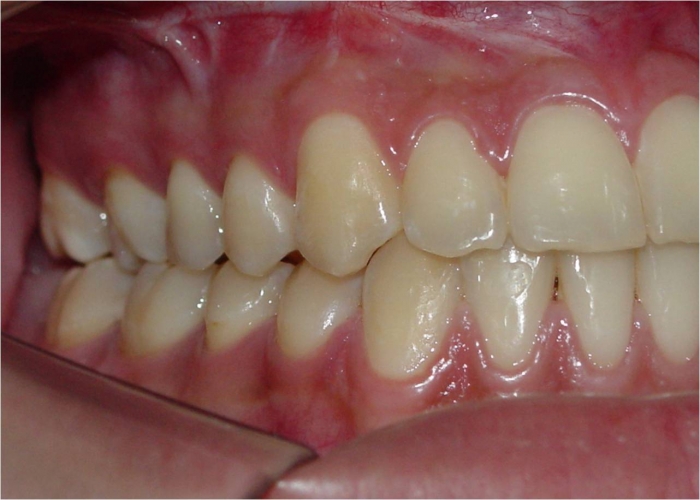

Mordida perfil inicial